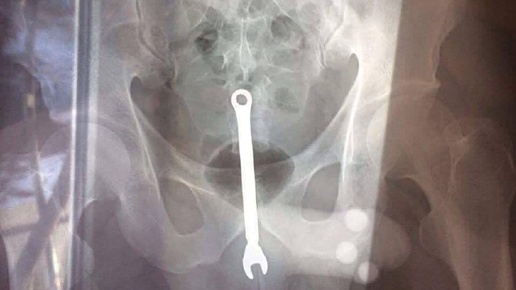

У него в заднице застрял гаечный ключ. Дважды. Михаил – его имя изменено – работник одной из автомобильных ремонтных мастерских, коих великое множество на окраинах столицы. В конце декабря Миша попал в больницу, – нетвёрдой походкой он сам явился к врачам и рассказал, что у него внутри ключ...

​​ Обычный московский автослесарь дважды за новогодние праздники оказался в больнице с гаечным ключом в заднем проходе. Как стало известно, он работник одной из автомобильных мастерских на окраине столицы...